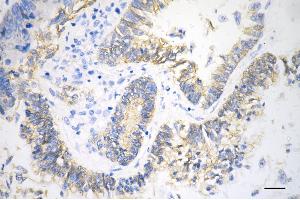

Choisissez l’un des 247 anticorps CTNNB1 de notre liste de produits basés sur 68 publications et 314 images de validation.

Découvrez des anticorps CTNNB1 fiables issus d’une large sélection de fabricants renommés. Notre portefeuille permet une détection précise de CTNNB1 dans plusieurs espèces, y compris Human, Mouse, Rat, Dog, Monkey, Chicken, Cow, Zebrafish (Danio rerio), Pig, Horse, Rabbit, Xenopus laevis, Hamster, Bat, Guinea Pig, Sheep, Opossum, et prend en charge diverses applications de recherche telles que WB, IHC, ELISA, IF, FACS.